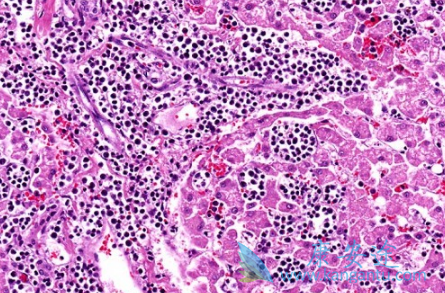

什么是血癌?血癌就是医学上的白血病,血癌只是一种俗称,在众多恶性肿瘤中,白血病是十大高发恶性肿瘤之一。那白血病传染吗?白血病是不会传染的,白血病主要是一种与血液有关的疾病,比如造血细胞出现了障碍,是造血系统的恶性肿瘤,主要与人的血液细胞有关,白血病不会传染但是却会遗传,家族里如果有一人患有白血病,那么家族的人遗传的几率为20%。

血癌常见症状有哪些?(1)淋巴结。全身广泛的淋巴结肿大,以急性淋巴细胞性白血病为多见,但急淋不如慢淋显着。浅表淋巴结在颈、颌下、腋下、腹股沟等处,深部淋巴结在纵隔及内脏附近。肿大的淋巴结一般质地软或中等硬度,表面光滑无压痛、无粘连。